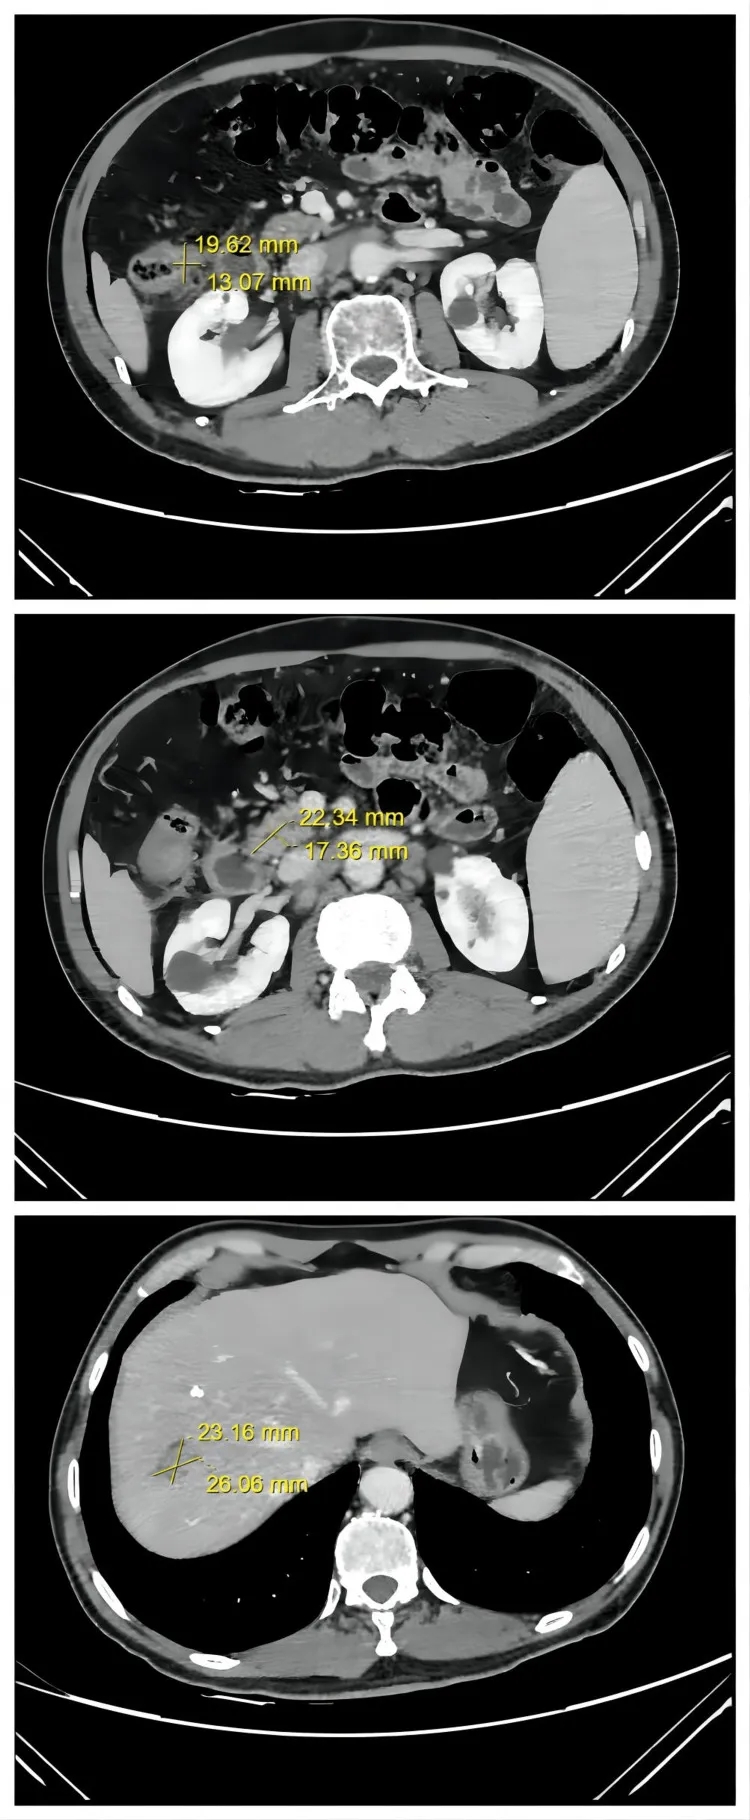

2、病灶全面缩小并达PR:相较于第二次治疗后“结肠及淋巴结病灶缩小、肝转移灶无变化”的情况,此次所有病灶均明显缩小——CT显示结肠肿瘤从3.7cm×3.1cm缩小至2.1cm×1.7cm,腹膜后淋巴结转移灶从5.2cm×4.3cm缩小至2.3cm×1.4cm,肝脏肿瘤从3.9cm×3.2cm缩小至2.9cm×2.3cm(详见下图)。肿瘤缩小至可手术切除的程度。术后,患者获得病理完全缓解(pCR)。

▼该患者第三次治疗后,腹部轴向CT图像

▲图源“Cureus”,版权归原作者所有,如无意中侵犯了知识产权,请联系我们删除